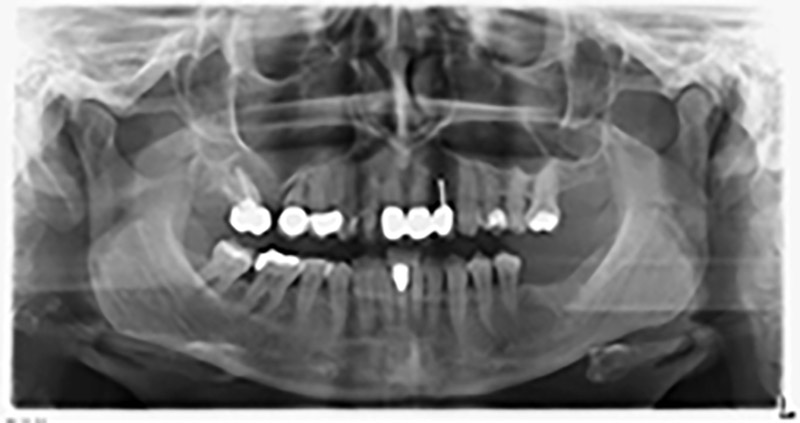

59-годишна пациентка с напреднал стадий на пародонтит описва неприятно чувство и лош вкус в първи квадрант в дисталната зона. Клиничният преглед разкрива силно уголемени пародонтални джобове и напреднала костна атрофия в зона 16 и 14. Рентгенографията потвърждава констатациите (Фиг. 1). Зъби 16 и 14 не могат да бъдат запазени.